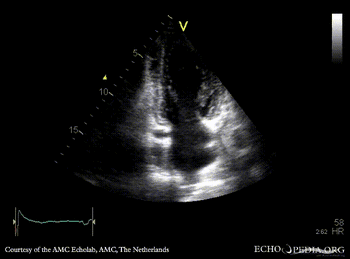

Diastloic dysfunction (pseudonormalisation)

A4CH: normal systolic function of left ventricle A2CH

A3CH Pulsed-wave Doppler signal of mitral inflow: E>A